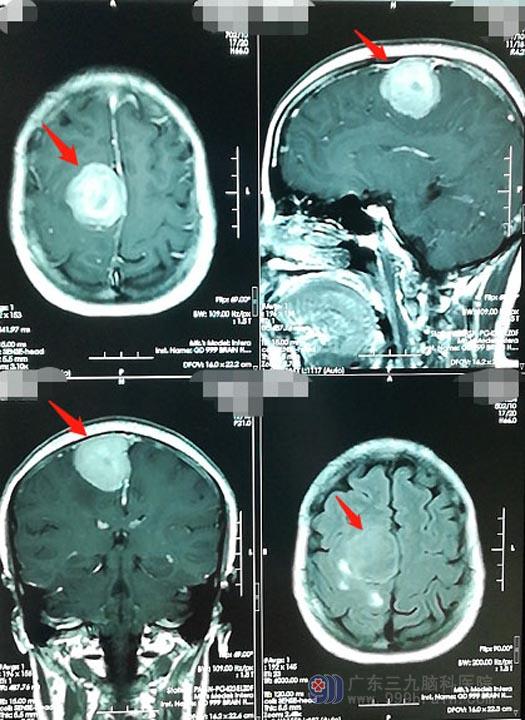

来到广东三九脑科医院神经外五科后,头颅MR、CTA等检查均显示是“右侧额顶部镰旁占位,考虑脑膜瘤”,体积约3.7cm×3.6cm×3.4cm。

覃阿姨的肿瘤位于中央沟处并突入上矢状窦内,属于脑功能区,手术稍有不慎很有可能导致患者对侧偏瘫。医院副院长、神经外五科主任鲁明带领团队制定了详细的手术方案并主刀手术。术中发现肿瘤已经侵犯长入上矢状窦内,与周围正常脑组织粘连紧密;术中切开静脉窦,将窦内的肿瘤一并彻底切除;再将静脉窦修补,静脉窦属于颅内大的引流静脉,血流丰富,修补过程既要考虑血管重建通畅情况又要避免出血较多及空气栓塞风险。最终,肿瘤被彻底切除,极大地避免了再复发的风险。这样的操作需要足够的技术与担当,只有对自身手术技术非常自信才能追求彻底的切除,否则可能会出现两种结果,要么损伤脑组织导致患者偏瘫,要么肿瘤残余遗留隐患。